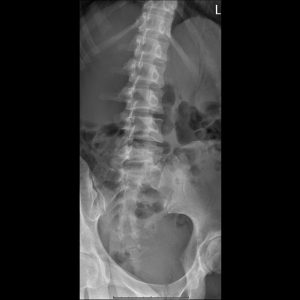

L-spine AP view